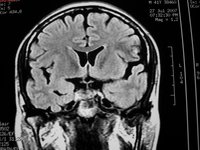

3、MRI表現

在腦部動靜脈畸形的診斷上有較大優越性,尤其是後顱窩病灶,診斷價值大於CT。因此,當懷疑病人患有腦血管畸形時,MRI為首選的影像檢查手段。①腦動靜脈畸形的血管成分,表現為成團狀、網狀分布的無信號流空血管影。其中供血動脈,在T1和T2加權像上因流空現象而表現為低信號或無信號影。引流靜脈則因血流緩饅,T1加權像呈低信號,T2加權像為高信號像。血管的鈣化表現為低信號或無信號暗區。動靜脈畸形中的血栓,在T1和T2加權像均表現為低信號夾雜等信號或高信號和低信號內夾雜高信號影。②動靜脈畸形出血形成血腫,則表現為T1和T2加權像變化和其他原因所致血腫相似。亞急性期血腫,在T1和T2加權像上均為高信號,隨時間延長,血腫在T1加權像上信號逐漸變為等信號或低信號,T2加權像上仍為高信號。

4、頭部MRI:優於CT,不僅能顯示畸形血管及其周圍腦組織,還可區別出血與鈣化。MRI血管造影相可提高畸形血管團的診斷率。

3、頭部磁共振:優於CT,不僅能顯示畸形血管及其與周圍腦組織的關係,還可區別出血與鈣化。